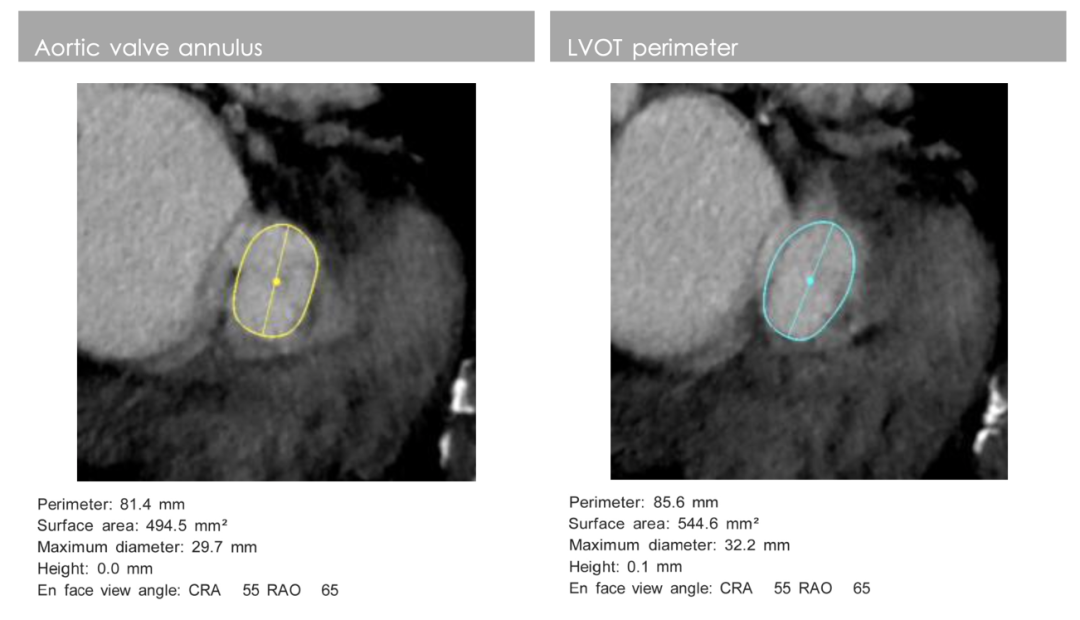

影像分析